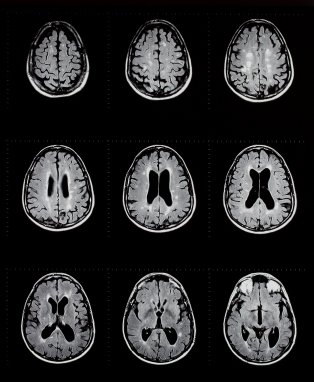

ДИАГНОСТИКА

Истории и физической будет выполнена. Испытания, проведенные в зависимости от обстоятельств захвата, особенно если это новая болезнь или уже существующие условия. Для пациентов, принимающих анти-захвата лекарства в крови могут быть измерены. Не все лекарства захват может быть измерена.

Медицинские процедуры, проводимые при заболевании эпилепсия: Уровень алкоголя в крови, Биохимический анализ крови, Электроэнцефалограмма, Спиральная компьютерная томография, Спинальная пункция, Магнитно-резонансная томография, Скринниг мочи на токсиныЛЕЧЕНИЕ И ПРОФИЛАКТИКА